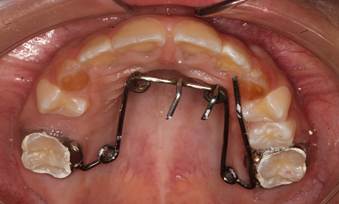

Figura 4. Análisis intraoral

Al examen intraoral se observa una mordida borde a borde de los incisivos antagonistas. La línea media dental inferior está desviada 1mm hacia la derecha. Piezas deciduas con signos clínicos de amelogénesis imperfecta.